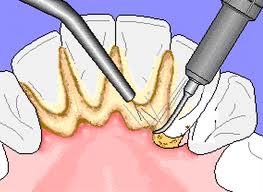

ขูดหินปูน เพื่อให้ฟันสะอาด ขจัดคราบแบคทีเรียที่ติดอยู่ตามตัวฟัน ร่องฟัน กระพุ้งแก้มและลิ้น ด้วยเครื่องมือที่ทันสมัย ปลอดภัย และ รวดเร็ว การขูดหินปูนควรทำอย่างน้อย 6 เดือนครั้ง เพื่อป้องกันการเกิดกลิ่นปาก ฟันผุและโรครำมะนาด อันเป็นเหตุให้ฟันโยกคลอนและหลุดออกได้